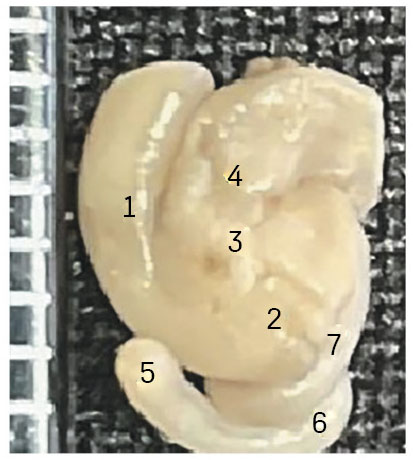

During macroscopic examination of the ileocecal intestinal region in fetuses with opened anterior abdominal wall, the transition zone between the terminal ileum and cecum, the cecum with its vermiform appendix, and the ileocecal orifice were clearly identifiable (Fig. 1).

Figure 1. Photo of a macro-preparation of the ileum-intestinal tract of the human fetus. Front view. ×7 magnification. Fetal age: 18–19 weeks, sex: male. 1 – ascending colon; 2 – dome of the cecum; 3 – ileocecal angle; 4 – ileum; 5 – tip of the appendix; 6 – third curl of the appendix; 7 – first curl of the appendix.

The position of the ileocecal region shows a slight vertical deviation (with some lateral inclination). The area of the ileocecal (cecocolic) angle is clearly identifiable for macroscopic examination and measurements.

In most cases (80%), the ileum enters the cecal lumen obliquely in a craniomedial direction, while in 20% of observations the entry orientation is horizontal, forming a 90° angle. At the fundus region, the cecum continues into the vermiform appendix either medially (75% of cases) or laterally (15%), without a distinct demarcation boundary.